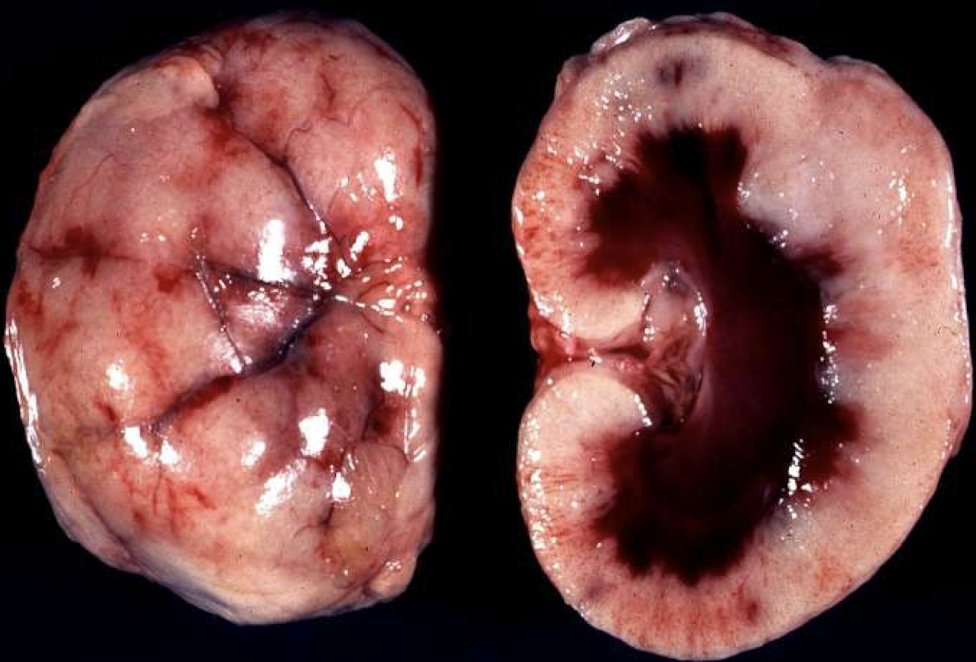

What gross features define acute hemorrhagic cystitis?

Dark red discoloration

Hemorrhage throughout mucosa

Often associated with bacterial infection or toxic injury

What gross features define Polycystic kidney disease?

Numerous, variably sized cortical and medullary cysts

Bilaterally enlarged kidneys

Replacement of parenchyma with cystic spaces